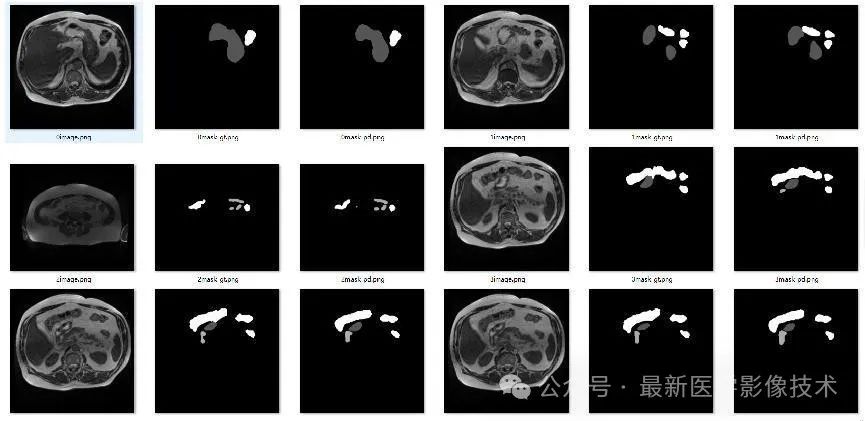

4、验证集部分分割结果